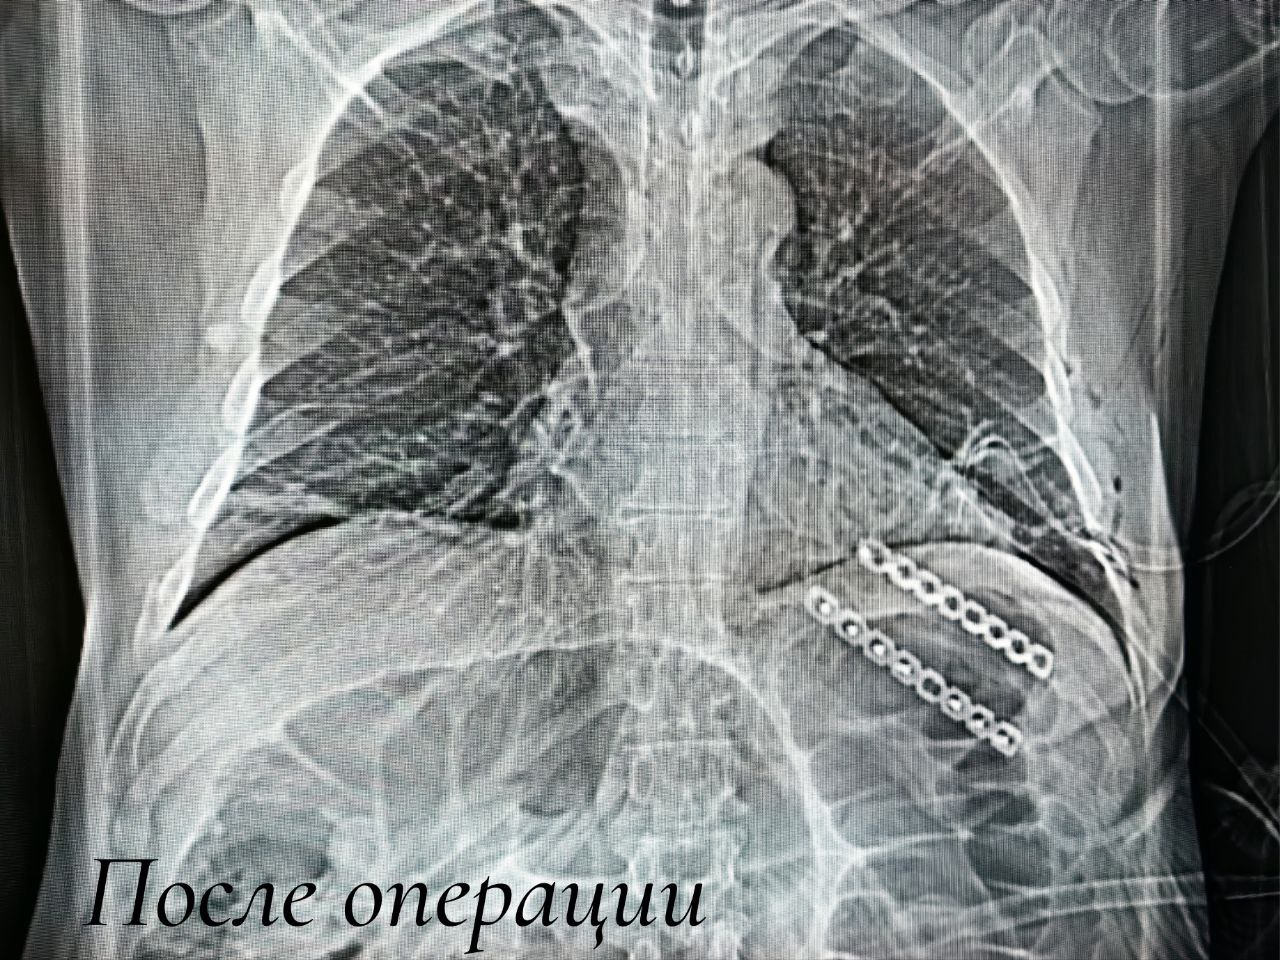

Сначала посредством малоинвазивного торакоскопического доступа выполнили пластику грыжи и вернули лёгочную ткань обратно в плевральную полость. Затем понадобился открытый доступ к месту перелома, чтобы устранить дефект рёбер. Их зафиксировали методом накостного остеосинтеза. Специальные пластины будут удерживать ребра в правильном положении, создавая условия для скорейшего сращения. Удалять конструкцию не потребуется. Восстановление пациента в раннем послеоперационном периоде прошло благополучно, сегодня он наблюдается амбулаторно.